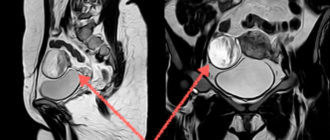

Можно ли заменить гистероскопию МРТ матки и яичников?

Мрт матки и яичников – что показывает и как проводится процедура? Ещё недавно диагностика